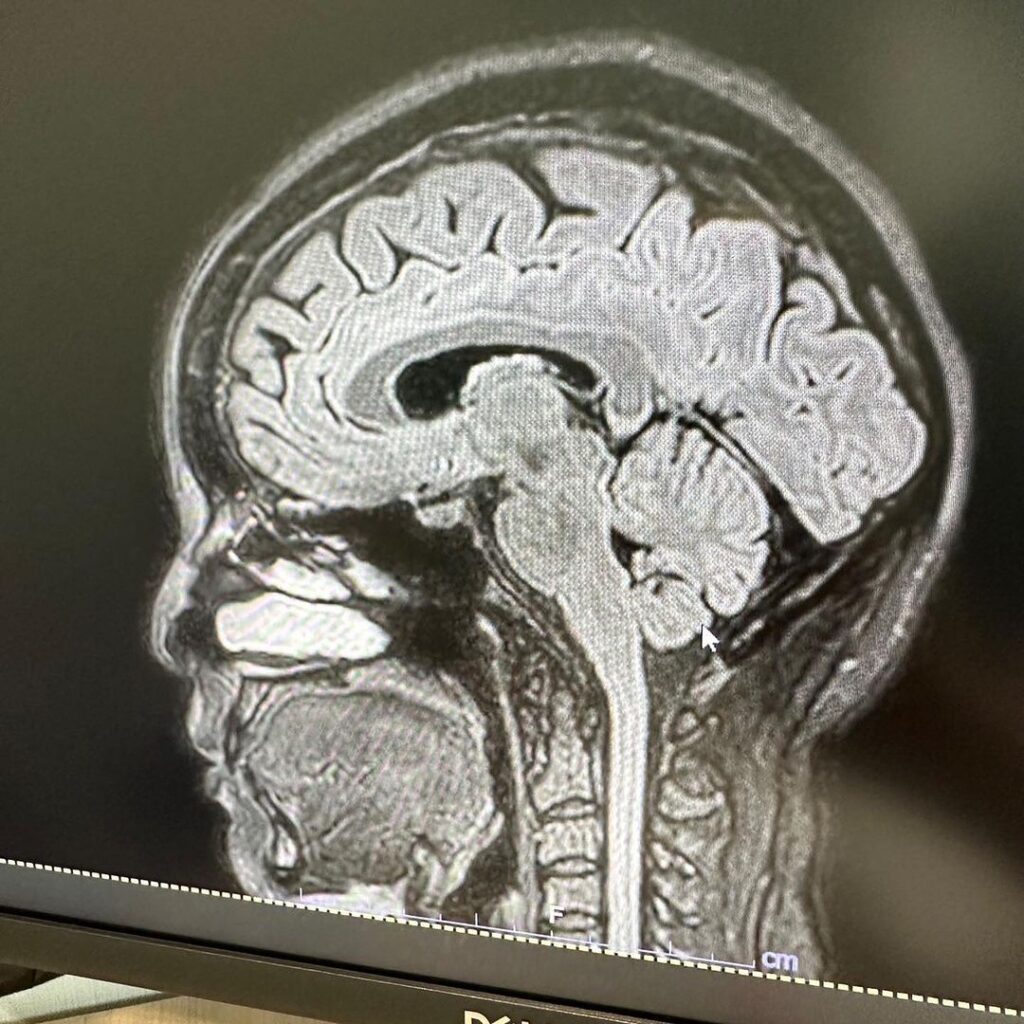

แต่ล่าสุดเจ้าตัวโพสต์ภาพสแกนสมอง หลังเข้ารับการรักษา ทำ MRI สมอง เนื่องจากมีอาการปวดหัวจัด จนกังวลใจคิดไปไกลกลัวจะเป็นเนื้องอก แต่สุดท้ายผลตรวจพบว่า เป็นไมเกรน ทำเอาเจ้าตัวโลงอก

“MRI สมอง เพราะปวดหัวมาก สรุปเป็นไมเกรน 😮💨 😵💫 นึกว่าเป็นเนื้องอก ลุ้นเเทบตาย โล่งอก😮💨 คุณหมอให้ยาฉีดที่ขาเเต่เป็นยาฉีดสำหรับไมเกรน ดีขึ้นเลย 💉เเต่ต้องฉีดต่อเนื่อง3-6เดือน ดีจังไม่ต้องทนปวดกินยาเเล้ว☺️”